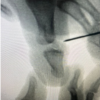

Our patient is a 42-year-old right-hand dominant female with a longstanding history of RA, SLE, Sjogren’s syndrome, and Raynaud’s syndrome who presented to hand clinic 3 days after developing the atraumatic inability to extend her left thumb at the MCP joint. She reported that the deformity was painless, had never occurred previously, and was associated with a clicking and popping sensation. She has suffered from joint pain since her mid-twenties, and her autoimmune conditions were being treated with methotrexate, hydroxychloroquine, and methylprednisolone, as well as a variety of biologics. On physical exam, the thumb was held in the boutonniere deformity, which was further provoked by the extension of the digit. A notable “clunk” was felt secondary to dorsal dislocation of the distal phalanx, which was passively but not actively reducible. With the MCP joint held reduced, her IP joint did not dislocate with active extension. She maintained full passive range of motion of the thumb MCP and IP joints, and there was no obvious subluxation of the EPL noted on inspection. Sensation to light touch was preserved throughout the median, ulnar, and radial nerve distributions, and the patient reported no pain. Radiographic views of the left thumb were obtained, demonstrating dorsal dislocation of the IP joint of the thumb and flexion at the MCP joint (Fig. 1). Clinical and radiological findings were consistent with severe boutonniere deformity of the thumb. The patient was provisionally provided a thumb spica brace to support the thumb in a corrected position, though she noticed recurrent dislocation as well as the emergence of pain over the next weeks.